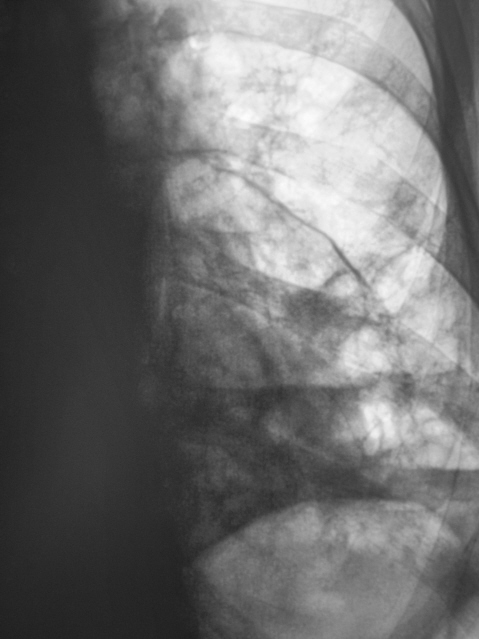

Абсцесс средней доли правого лёгкого (в процессе лечения).

Абсцесс средней доли правого лёгкого.